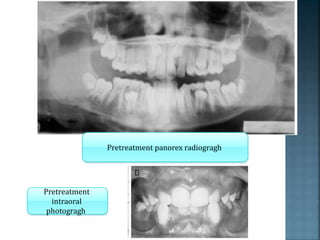

Pretreatment panorex radiogragh

Pretreatment

intraoral

photogragh

Pretreatment periapical x-ray of maxillary central

incisors

Progress panorex radiogragh

Final intraoral photogragh

Final periapical radiogragh of maxillary central